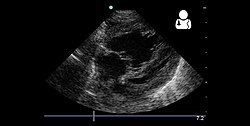

Echocardiography[edit | edit source]

If pulmonary hypertension is suspected based on the above assessments, echocardiography is performed as the next step.[10][11][53] A meta-analysis of Doppler echocardiography for predicting the results of right heart catheterization reported a sensitivity and specificity of 88% and 56%, respectively.[55] Thus, Doppler echocardiography can suggest the presence of pulmonary hypertension, but right heart catherization (described below) remains the gold standard for diagnosis of PAH.[10][11] Echocardiography can also help to detect congenital heart disease as a cause of pulmonary hypertension.[10]